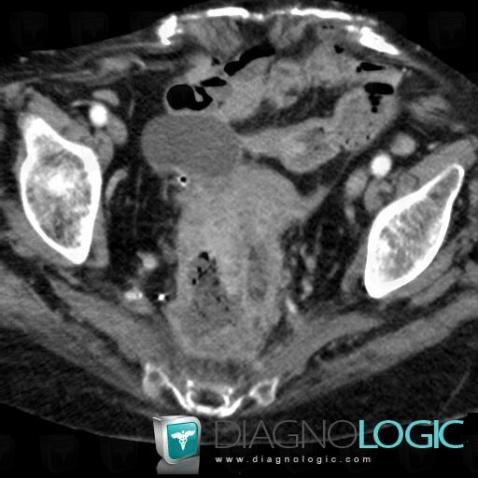

Rectal cancer, Rectum, Pelvis / Perineum, CT

Here is the specific information in the key image above:

- Diagnosis Rectal cancer, Location(s) Rectum, with gamuts Presacral massPelvis / Perineum, with gamuts Presacral mass